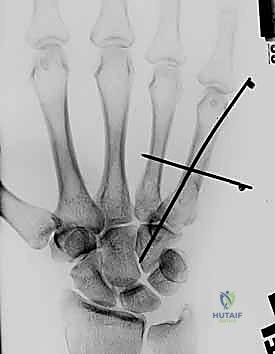

1. التثبيت باستخدام الأسلاك الدقيقة (K-wires)

تُعد هذه الطريقة (Percutaneous Pinning) من التقنيات طفيفة التوغل. يتم إدخال أسلاك معدنية رفيعة جداً عبر الجلد لتثبيت العظم المكسور تحت توجيه الأشعة السينية المستمرة (C-arm) داخل غرفة العمليات.

* الميزة: جروح صغيرة جداً، تعافٍ أسرع للأنسجة الرخوة.

* الإزالة: غالباً ما يتم إزالتها في العيادة بعد 4-6 أسابيع بدون الحاجة لتخدير كامل.

خطوات التثبيت الجراحي - توثيق بصري (Intraoperative Imaging)

يحرص الدكتور هطيف على توثيق خطوات العمل الجراحي لضمان أعلى مستويات الدقة. نستعرض هنا مجموعة من الصور من داخل غرفة العمليات توضح مدى تعقيد ودقة هذه الجراحات:

معرض الصور الشعاعية: تقييم النتائج الجراحية (Post-Op X-rays)

النجاح الحقيقي يُقاس بالاستعادة المثالية للشكل التشريحي للعظم. توضح هذه الصور الشعاعية بعد الجراحة الدقة المتناهية في إعادة محاذاة العظام وتثبيتها.

التثبيت المحكم يسمح بالشفاء العظمي الأولي (Primary Bone Healing) دون تكوين كتلة عظمية كبيرة (Callus) قد تعيق حركة الأوتار المنزلقة فوقها.

أصيب المريض بكسر سحقي (Crush injury) أدى إلى تفتت العظمة المشطية الخامسة مع انحراف دوراني (Scissoring). تم إجراء جراحة دقيقة بواسطة الأسلاك (K-wires) لإعادة بناء العظم. التزم المريض ببرنامج التأهيل الصارم الموصى به، واستعاد وظيفة يده بالكامل ليعود إلى عمله الفني الدقيق دون أي إعاقة حركية.